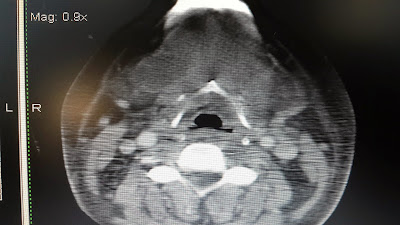

Se solicitó una TAC de región facial, cuello, y tórax.

Se

informó la TAC como refuerzo en espacio sublingual especialmente

derecho con refuerzo periférico de contraste compatible con

absceso/flemón de piso de la boca. Los espacios masticatorios pre y

post estiloideos, prefaríngeos y retrofaríngeos no muestran imágenes

agregadas.

Imágenes ganglionares de aspecto reactivo y en rango no adenomegálico en localización yúgulo-carotídeo bilaterales.